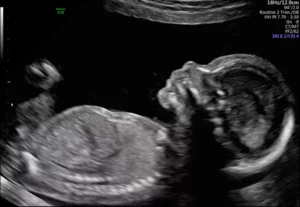

Fetal ultrasound morphology - from 20. to 24th week of pregnancy

Fetal morphology ultrasound is one of the the most important ultrasound examinations in pregnancy. It is usually carried out between 20 and 24 weeks of pregnancy and represents a detailed overview of the child's anatomy and the development of the organs. The purpose of the examination is to check whether the foetus is growing and progressing according to its gestational age and to identify whether there are any structural or developmental complications.

During the morphological examination, the gynaecologist makes a detailed assessment of the head and brain (the shape of the head, brain structures, brain chambers, cerebellum and other important anatomical features are examined), face (the eyes, nasal bone, lips are examined (possible cleft

lips or sky)), back and spine (the whole spine is checked to rule out an open neural tube defect (spina bifida)), heart (a detailed examination of the four cavities of the heart, the draining vessels, the heart rhythm and any heart defects), the abdomen and internal organs (stomach, kidneys, bladder, abdominal wall, intestines and umbilical cord (number of blood vessels) are looked at), extremities (examination of arms and legs, measurement of bones (humerus, femur), symmetry and movement), condition of postelina and amniotic fluid quantity (assessing the position and thickness of the placenta and the sufficiency of the amniotic fluid); and fetal growth (body measurements (e.g. head circumference, abdominal circumference, bone lengths) are taken to assess whether the foetus is growing in line with gestational age). on review four heart cavities and the draining vessels, as this rules out the most common congenital heart defects. If necessary, it is also used Doppler ultrasoundwhich allows you to check the flow in the umbilical cord and other vessels.